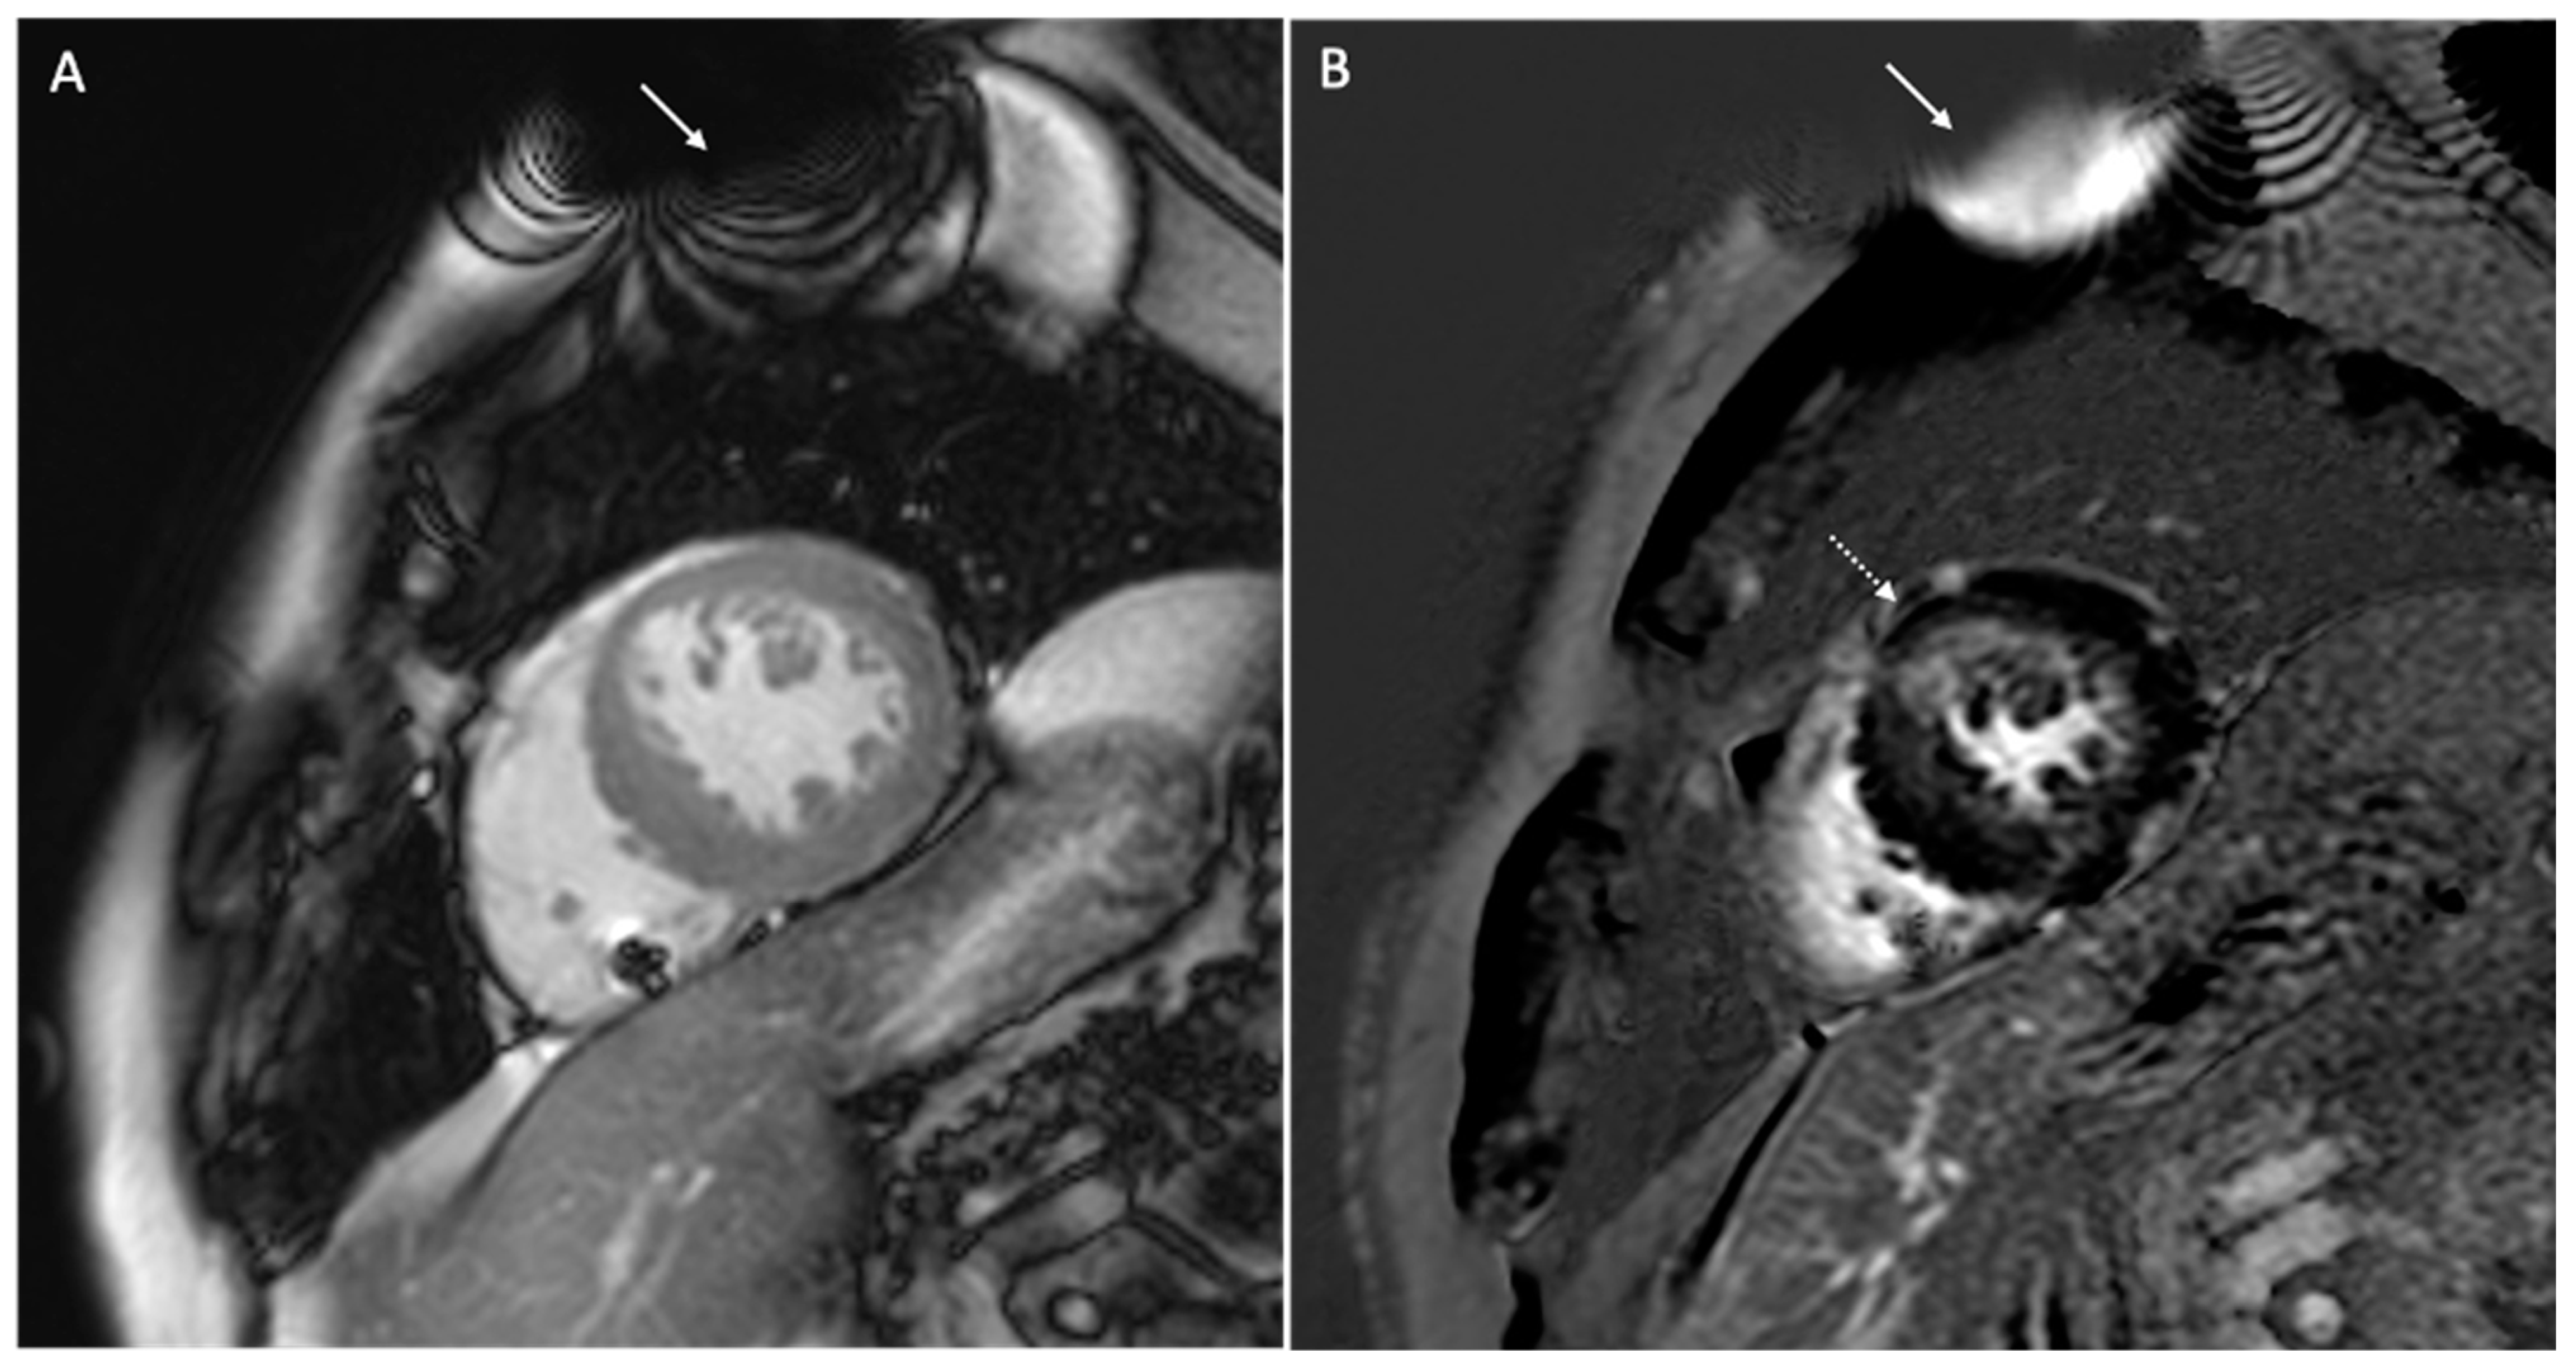

- Vuorinen, A.-M.; Lehmonen, L.; Karvonen, J.; Holmström, M.; Kivistö, S.; Kaasalainen, T. Reducing cardiac implantable electronic device–induced artefacts in cardiac magnetic resonance imaging. Eur. Radiol. 2022, 33, 1229–1242. [Google Scholar] [CrossRef] [PubMed]

- Runge, M.; Ibrahim, E.-S.H.; Bogun, F.; Attili, A.; Mahani, M.G.; Pang, Y.; Horwood, L.; Chenevert, T.L.; Stojanovska, J. Metal Artifact Reduction in Cardiovascular MRI for Accurate Myocardial Scar Assessment in Patients with Cardiac Implantable Electronic Devices. Am. J. Roentgenol. 2019, 213, 555–561. [Google Scholar] [CrossRef]

- Ibrahim, E.-S.H.; Runge, M.; Stojanovska, J.; Agarwal, P.; Ghadimi-Mahani, M.; Attili, A.; Chenevert, T.; Harder, C.D.; Bogun, F. Optimized cardiac magnetic resonance imaging inversion recovery sequence for metal artifact reduction and accurate myocardial scar assessment in patients with cardiac implantable electronic devices. World J. Radiol. 2018, 10, 100–107. [Google Scholar] [CrossRef]